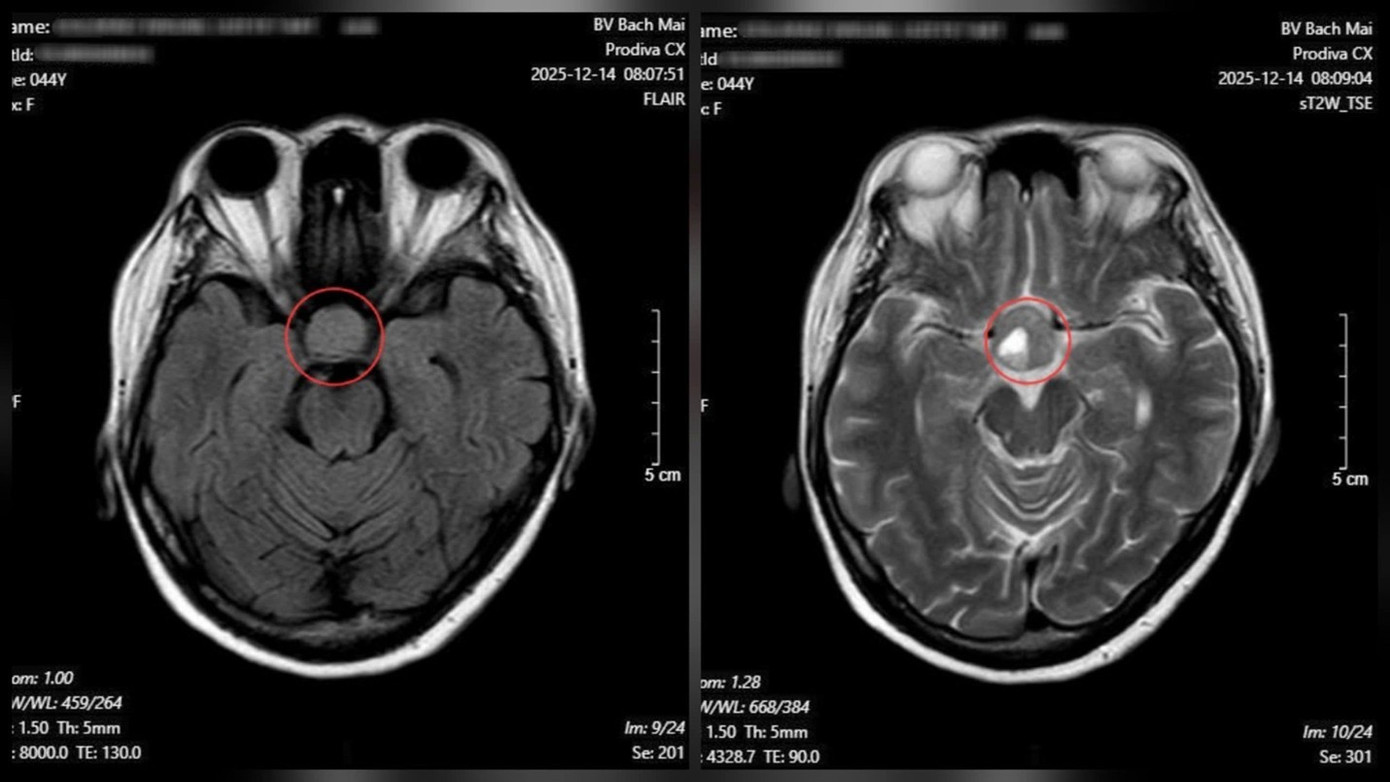

Từ các dấu hiệu nghi ngờ, bệnh nhân được chỉ định chụp cộng hưởng từ (MRI) sọ não. Kết quả cho thấy một khối u tuyến yên kích thước lớn (macroadenoma) với đường kính khoảng 26 × 21 mm, đang chèn ép cấu trúc thần kinh thị giác.

Nhìn mờ kéo dài, người đàn ông phát hiện bệnh lí nguy hiểm- Ảnh 2.

Kết quả chụp cộng hưởng từ (MRI) sọ não cho thấy một khối u tuyến yên kích thước lớn